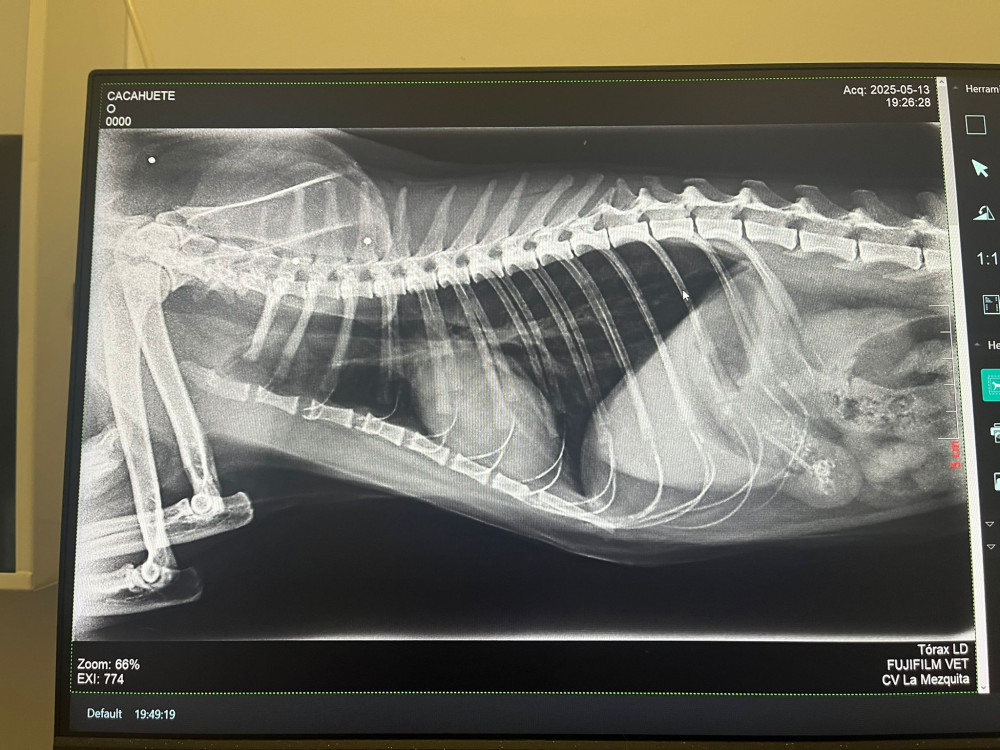

Lo rescatamos desde Francia, y, al llegar aquí, nos encontramos con este panorama desolador para él:  una auténtica barbaridad de perdigones en el cuerpo y una cardiopatía ❤️‍🩹 Las imágenes hablan por sí solas...